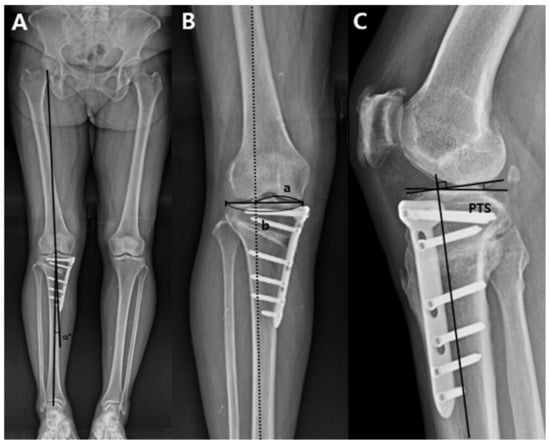

Three major variables were measured in the 3D reconstructed model: (1) the preoperative and postoperative posterior tibial slope, (2) osteotomy inclination angle relative to the medial tibial plateau line in the sagittal plane, and (3) anterior and posterior opening gap and the ratio of these two osteotomy gaps. To measure the posterior tibial slope and osteotomy inclination angle in the sagittal plane, the 3D reconstructed model was aligned in a true lateral position. The true lateral position of the tibia was obtained by manipulating the femoral lateral and medial condyles to be superimposed on the basis of the method presented in a previous study [24]. When measuring variables, the 3D model of the femur was made invisible for convenience. After the true lateral view was completed, this view was captured because these two lines could not be located on the same plane. The posterior tibial slope was measured on the captured 3D true lateral view as previously described [25,26]. The line perpendicular to the bisecting line of the tibial shaft and the medial tibial plateau line were drawn. The angle formed by these two lines was defined as the posterior tibial slope (Figure 2A). To measure the preoperative original posterior tibial slope, the original tibia model was obtained by removing the osteotomy gap of the proximal tibia. The proximal and distal parts of the tibia were combined to the preoperative original tibia by rotating the proximal segment using the lateral cortex as a hinge. The original posterior tibial slope was measured in the same way (Figure 2B). To measure the osteotomy inclination angle in the sagittal plane, a medial tibial plateau line and a sagittal osteotomy line on the anteromedial aspect of the lowermost part of the proximal tibia segment were drawn on the captured 3D true lateral view. The angle formed by these two lines was defined as the osteotomy inclination angle (Figure 3A) [19]. When the front of the osteotomy line was inclined downward with respect to the line parallel to the medial tibial plateau, it was classified as positive, and if it was inclined upward, it was classified as negative. The osteotomy gap ratio was defined as the ratio between the distances of the anterior opening gap and posterior opening gap in the 3D reconstructed model. The anterior opening gap was measured at the medial edge of the frontal plane osteotomy site. The posterior opening gap was measured at the most prominent posteromedial edge of the tibia (Figure 3B) [17,27]. The osteotomy gap ratio (%) was calculated by dividing the anterior opening gap by the posterior opening gap and multiplying by 100. Measurements of variables were conducted by two independent orthopedic surgeons who did not participate in the MOWHTO and were blinded to the patients’ information to increase their reliability. The mean of the two numerical values was used.

Figure 3. Measurement of the sagittal osteotomy inclination angle and anterior and posterior opening gap in a three-dimensional reconstructed model. (A) The sagittal osteotomy inclination angle was measured as the angle formed by the medial tibial plateau line (black dotted line) and osteotomy line on the anteromedial aspect of the lowermost part of the proximal tibial segment (black solid line) on the true lateral view. (B) Distances of anterior opening gap and posterior opening gap were measured in the three-dimensional reconstructed model. The anterior opening gap was measured at the medial edge of the frontal plane osteotomy site. The posterior opening gap was measured at the most prominent posteromedial edge of tibia.